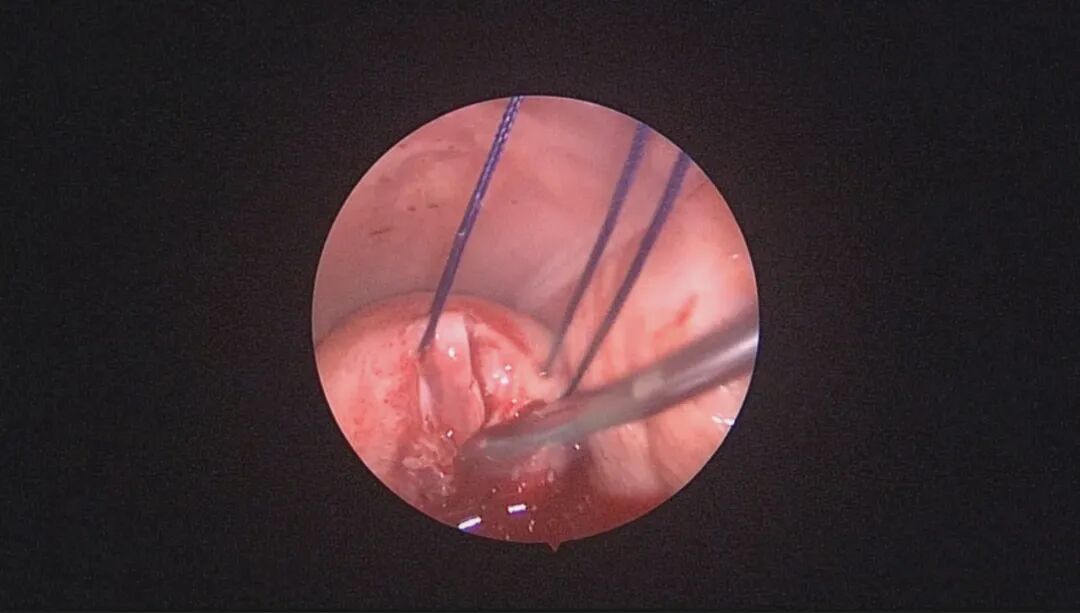

外院取环失败,宫颈暴露困难,缝合牵拉宫颈,尖刀片切开宫颈前唇,扩宫棒顺利扩开宫颈